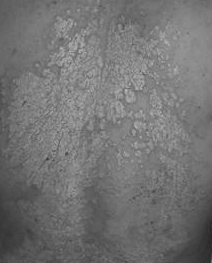

1、皮肤癣之花斑癣

花斑癣是由寄生于表皮角层的花斑癣菌所引起的,惯发于颈和胸背部位。有时,上肢近端也被波及。基本损害为斑疹,大小如黄豆。新疹是黄褐色或棕褐色,旧的病变呈灰白色。皮损表面附有微量糠状鳞屑,相邻皮诊可互为融合成较大的不规则病灶。一般无自觉症状,偶尔出汗时稍有痒感。